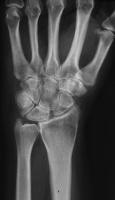

| This woman in her 30's presented with left wrist pain and was found to have inflammatory osteoarthritic changes throughout her wrist, distal radioulnar joint and thumb basal joint. Blood tests were normal, including rheumatoid factor, antinuclear antibody, sedimentation rate, uric acid, and complete blood count. She was treated with nonsteroidal oral antiinflammatory medication and splints. |

| Initial Films: |